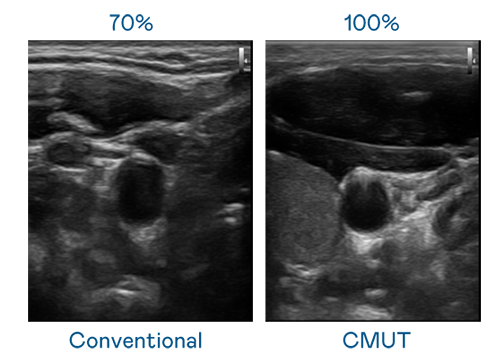

CMUT 技術是一種用電容式微機電元件來產生超音波訊號的技術。與傳統 PZT 壓電式技術相比,CMUT 頻寬增加 30%,更寬頻的超音波訊號讓影像解析度大幅提升,是實現高影像品質醫療超音波掃描、促進精準醫療發展的關鍵技術。

超音波影像的解析度高低,首先取決於探頭能發出的訊號頻寬。MK体育 CMUT 可提供高清晰的超音波訊號,提供高頻寬、高靈敏度、影像紋理細節更高的超音波影像,協助醫護人員縮短影像判讀時間及利用精準的醫療影像進行診斷。